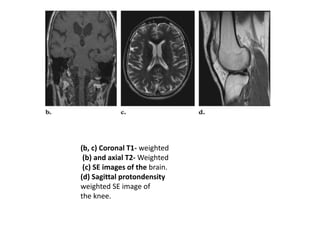

(b, c) Coronal T1- weighted

(b) and axial T2- Weighted

(c) SE images of the brain.

(d) Sagittal protondensity

weighted SE image of

the knee.